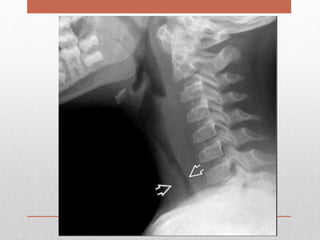

• A lateral plain film of the neck showed soft tissue

swelling anterior to the vertebral bodies

• lateral neck radiograph may show an

increase in width of the soft tissues anterior to the

vertebrae.

Case 3 : •2 years old child presented to the emergency department with a one-week history of URI symptoms and a one-day history of more severe throat pain and swelling. • Upon physical examination the patient was febrile and although she did not demonstrate any signs of respiratory distress, examination of her neck revealed fullness on the right. • A lateral plain film of the neck showed soft tissue swelling anterior to the vertebral bodies